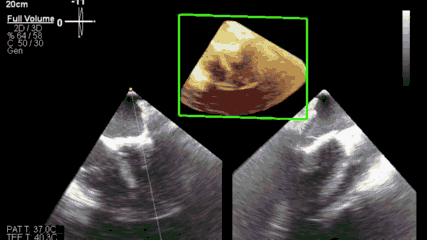

△ 术后三维心超示人工二尖瓣位置良好

手术在中山医院心脏外科复合手术室内完成,全程DSA与三维经食道超声心动图监测。全部操作时间约一小时,其中心尖穿刺至瓣膜释放成功仅耗时约10分钟。瓣膜释放位置完美、固定牢靠、功能良好,术毕二尖瓣反流立刻消失,无瓣周漏、无冠脉压迫、无左室流出道梗阻、无传导阻滞。术后4小时患者即脱离呼吸机支持,20小时后回到普通病房并下床活动。